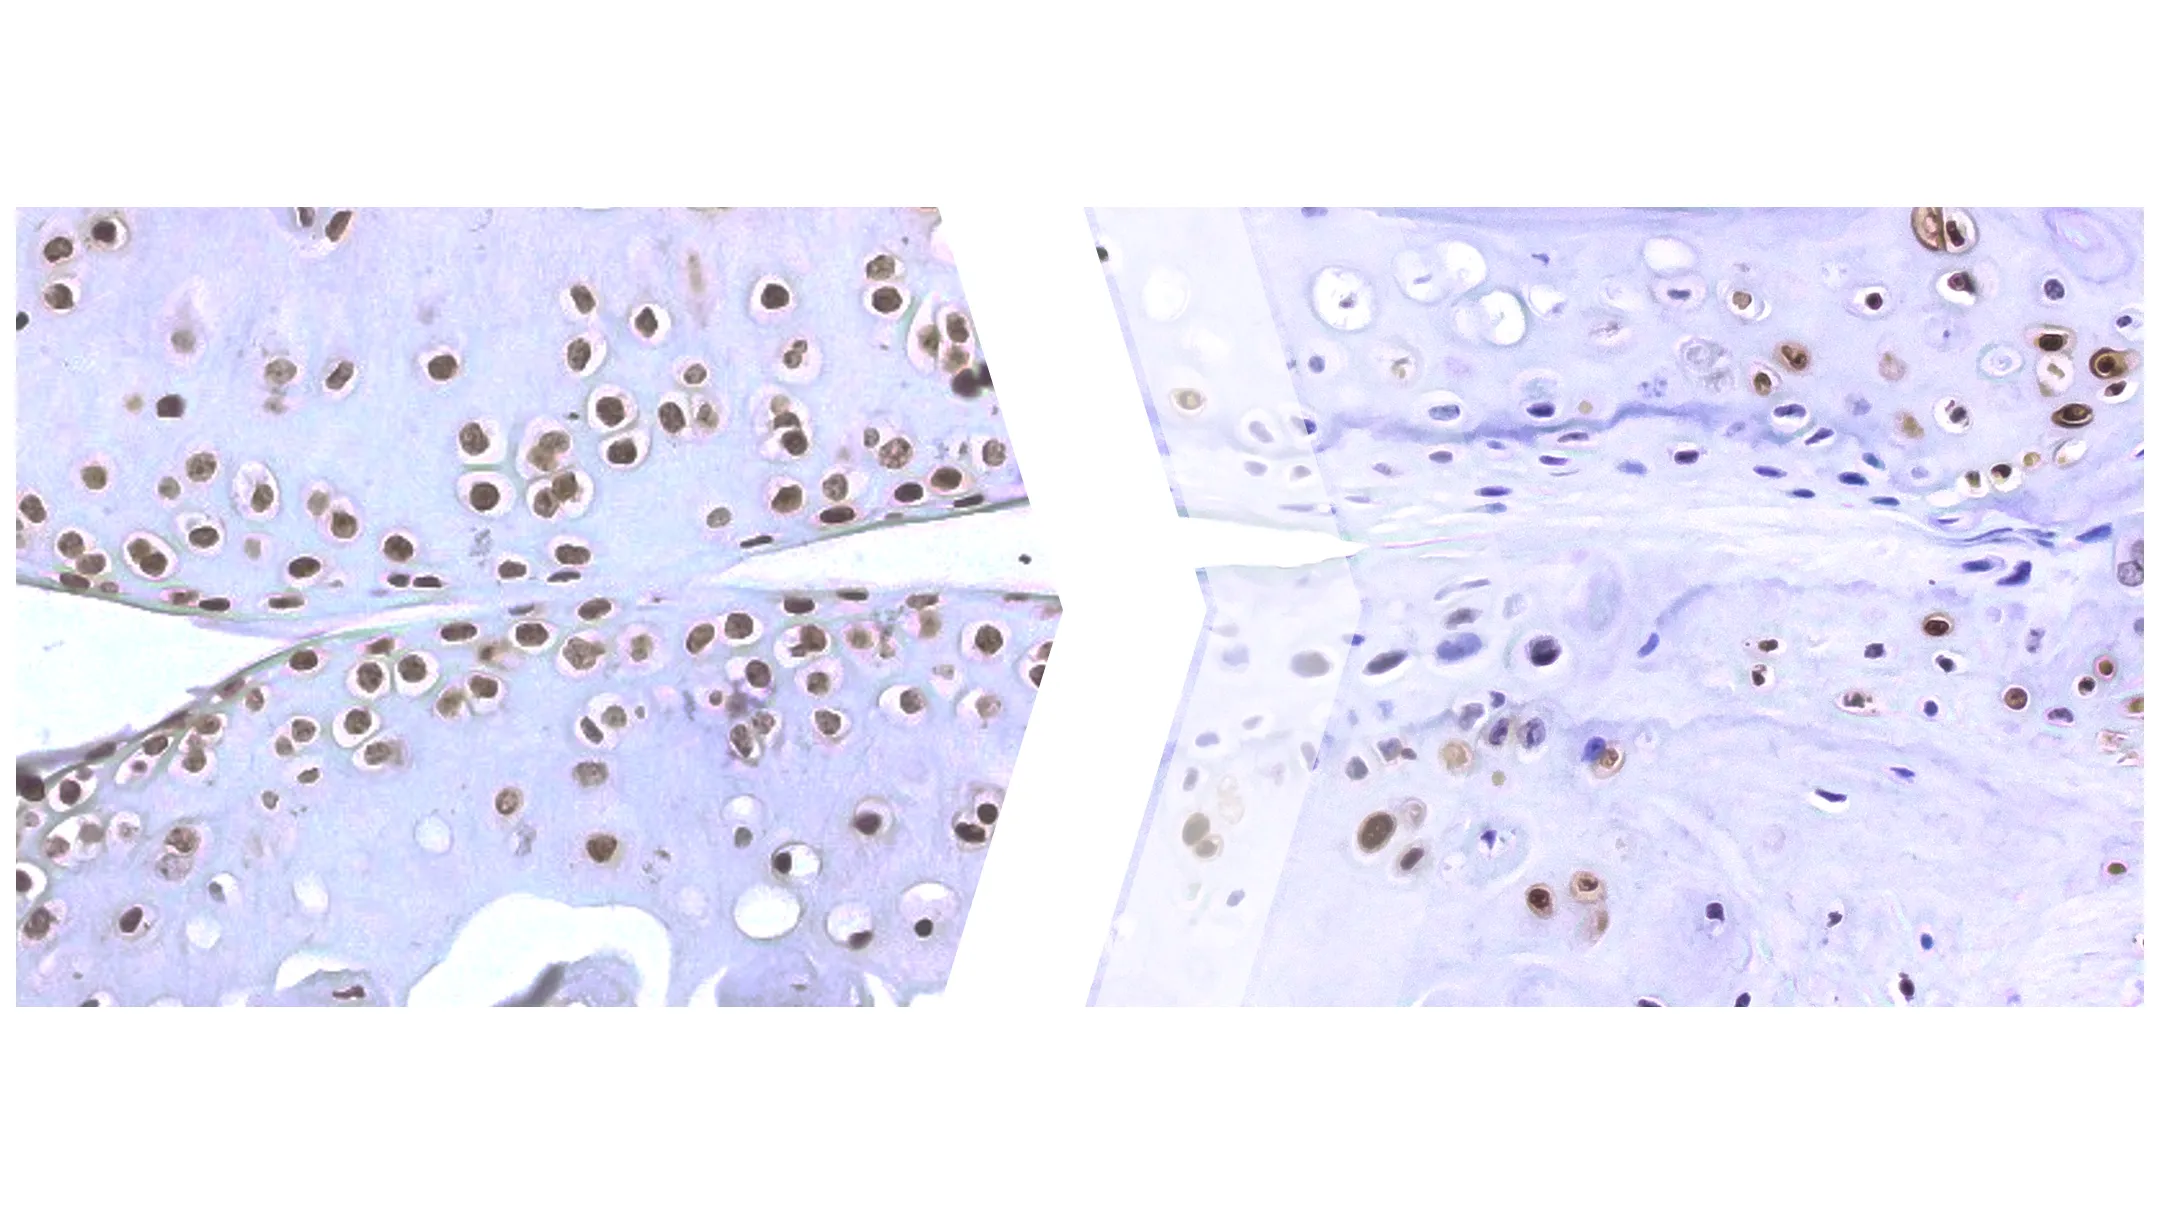

March 4, 2025 Could silencing old viruses help treat osteoarthritis?

April 19, 2023 Osteoporosis treatments may benefit from discovery of key driver of low bone density

GRAND RAPIDS, Mich. (April 19, 2023) — Van Andel Institute scientists have pinpointed a key driver of low bone density, a discovery that may…